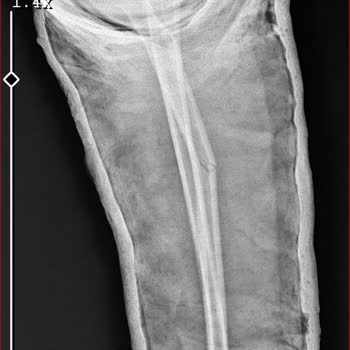

5 Eylül 2025 tarihinde saat 11.10 sularında yaşadığım bir kaza sonucu elimde kesikler oluştu ve f. S. M Hastanesi acil servisine başvurdum. Elim kanarken, acil serviste yaklaşık 1 saat bekletildim ve 1 cm’lik açık kesik ancak 1 saat sonra dikildi. Dikişi atan doktor, elim kanar haldeyken ve kesik aç...